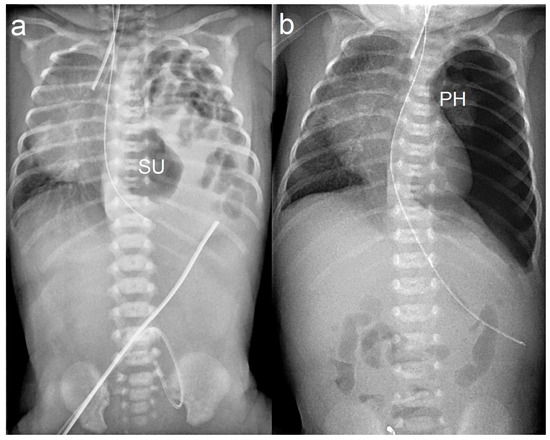

| 6 | M | 37 | 2930 | Pulmonary hypertension | No | 6 | 2900 | Thoracoscopic | 288 | Left posterior, Type C | Up | Yes, PTFE-collagen Combination | Sutures pulled back and damaged diaphragmatic tissue because of saw effect; therefore, PTFE patch placed | 3-0 V-Loc permanent | 38 | 18 | Developed Bell stage IIb necrotizing enterocolitis postop, no recurrence, doing well |